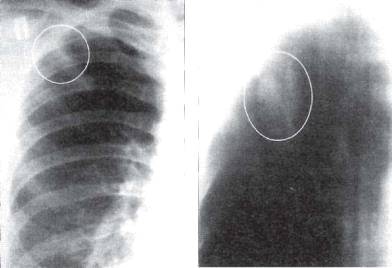

а б

Рис. 11.6. Округлый инфильтрат во II сегменте

правого легкого (а) и во II сегменте левого легкого (б). Фрагменты

рентгенограмм легких в прямой проекции.

Рис. 11.7. Инфильтрат Ассманна-Редекера в левом

легком. Фрагменты рентгенограмм легких в прямой проекции.

На обзорной рентгенограмме в прямой проекции затемнение часто локализуется в подключичной области (классический тип инфильтрата Ассманна-Редекера, рис. 11.7). От медиальных отделов затемнения к корню легкого отходит воспалительная дорожка, в которой иногда выявляют проекцию дренирующего бронха (симптом «теннисной ракетки» - рис. 11.8, 11.9). При распаде инфильтрата в его центральных отделах обычно выявляются образовавшиеся полости (рис. 11.10). В нижележащих отделах легкого нередко заметны очаги бронхогенного обсеменения. При томографии в инфильтрате иногда можно обнаружить плотные и кальцинированные очаги - важный признак туберкулезной этиологии поражения.